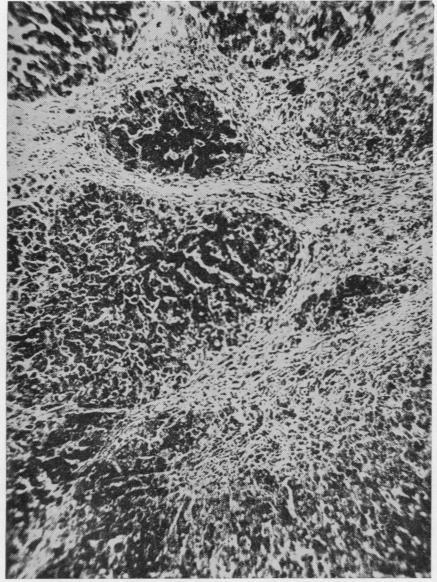

A case of paroxysmal nocturnal haemoglobinuria associated with secondary haemochromatosis, a lower nephron nephrosis, and a megaloblastic anaemia.

J Clin Pathol. 1955 Aug;8(3):211-7. doi: 10.1136/jcp.8.3.211.